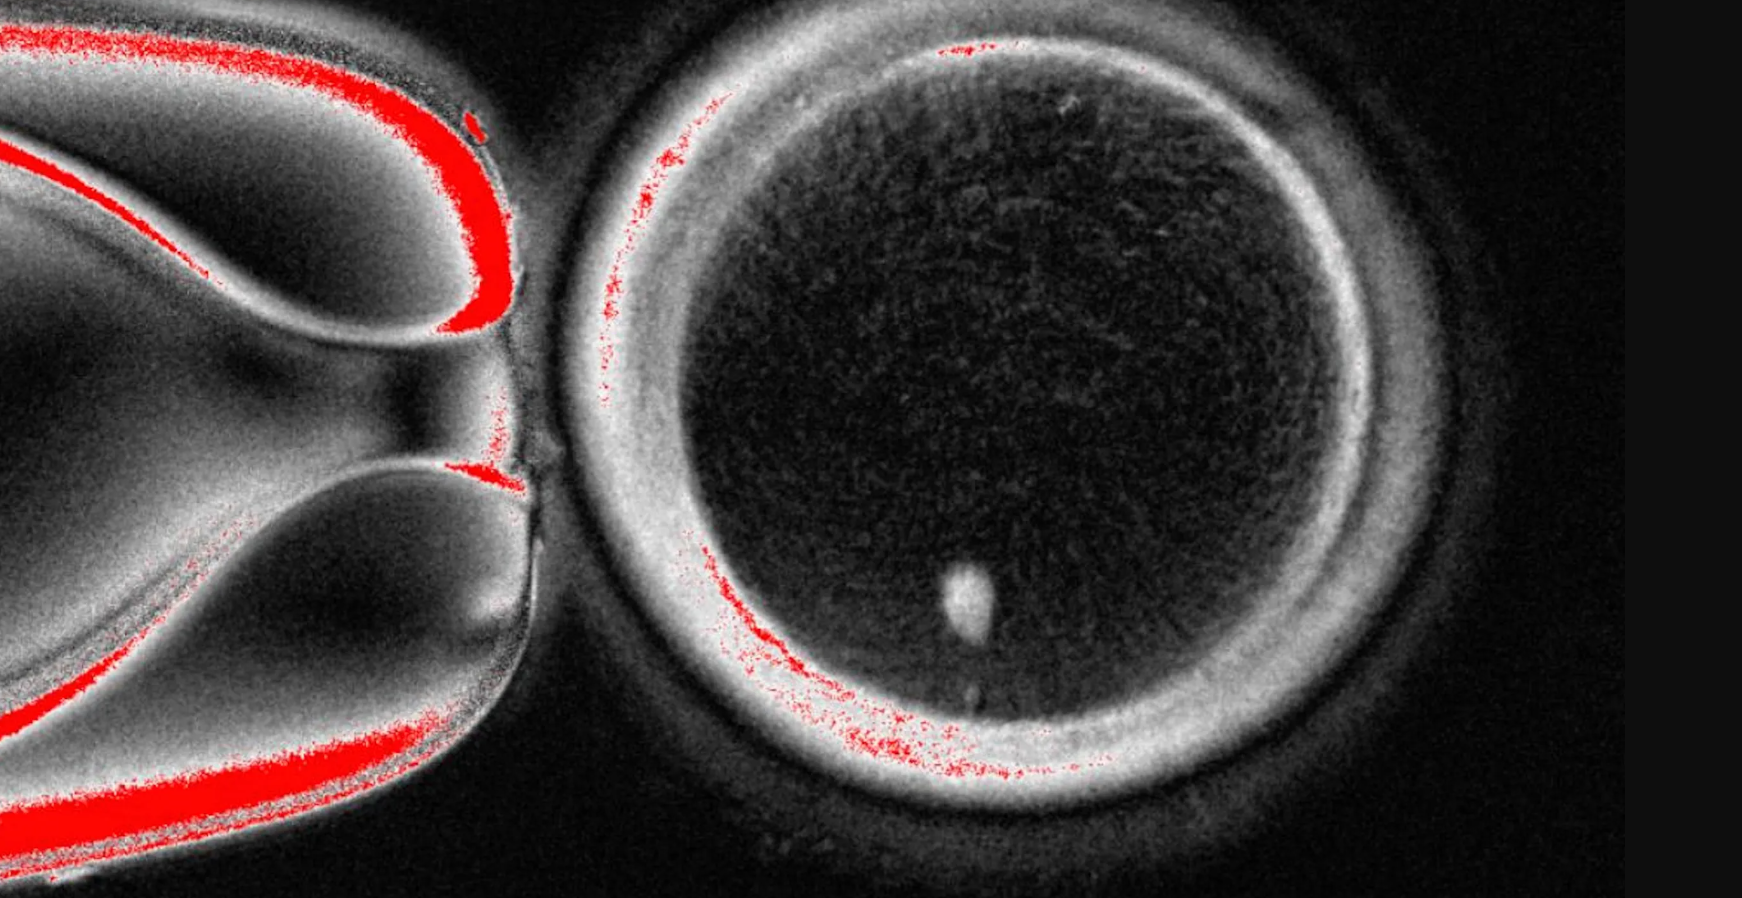

গবেষক দলটি প্রথমে স্বেচ্ছাসেবীদের কাছ থেকে ডিম্বাণু সংগ্রহ করে তাদের নিউক্লিয়াস অপসারণ করেন। তারপর অন্য স্বেচ্ছাসেবীদের ত্বকের কোষ সংগ্রহ করে সেগুলোর মধ্যে থেকে পৃথক কোষ ডিম্বাণুর সঙ্গে যুক্ত করেন।

এই পদ্ধতিতে ৮২টি SCNT ডিম্বাণু তৈরি করা হয়, এবং পরে তা শুক্রাণুর মাধ্যমে নিষিক্ত করা হয়। এর মধ্যে ৫টি ডিম্বাণু ভ্রূণের প্রাথমিক স্তর ব্লাস্টোসিস্ট-এ উন্নীত হয়, এরপর পরীক্ষা বন্ধ করা হয়।